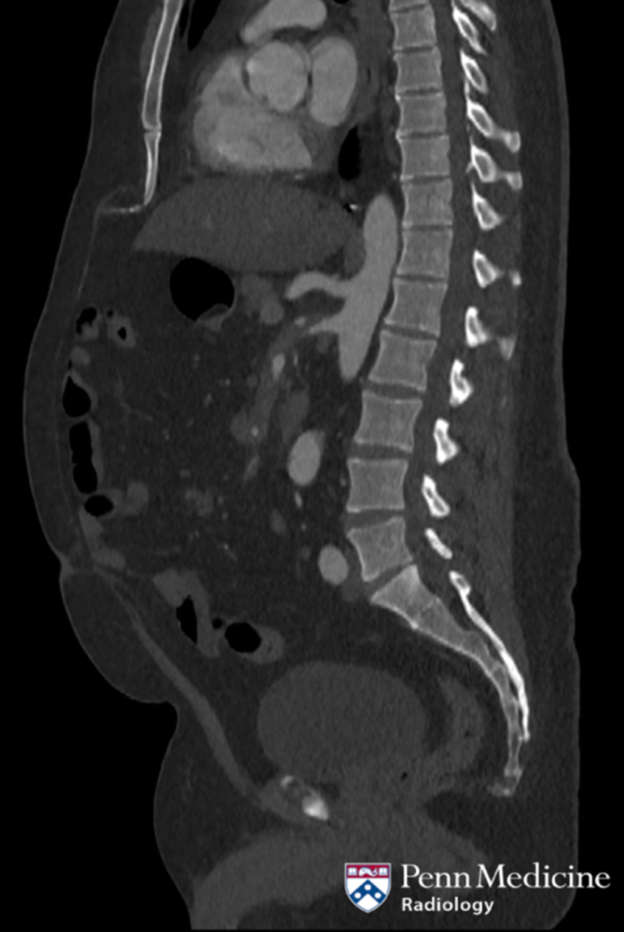

48-year-old man with abdominal pain

A 48-year-old man presented with abdominal pain.